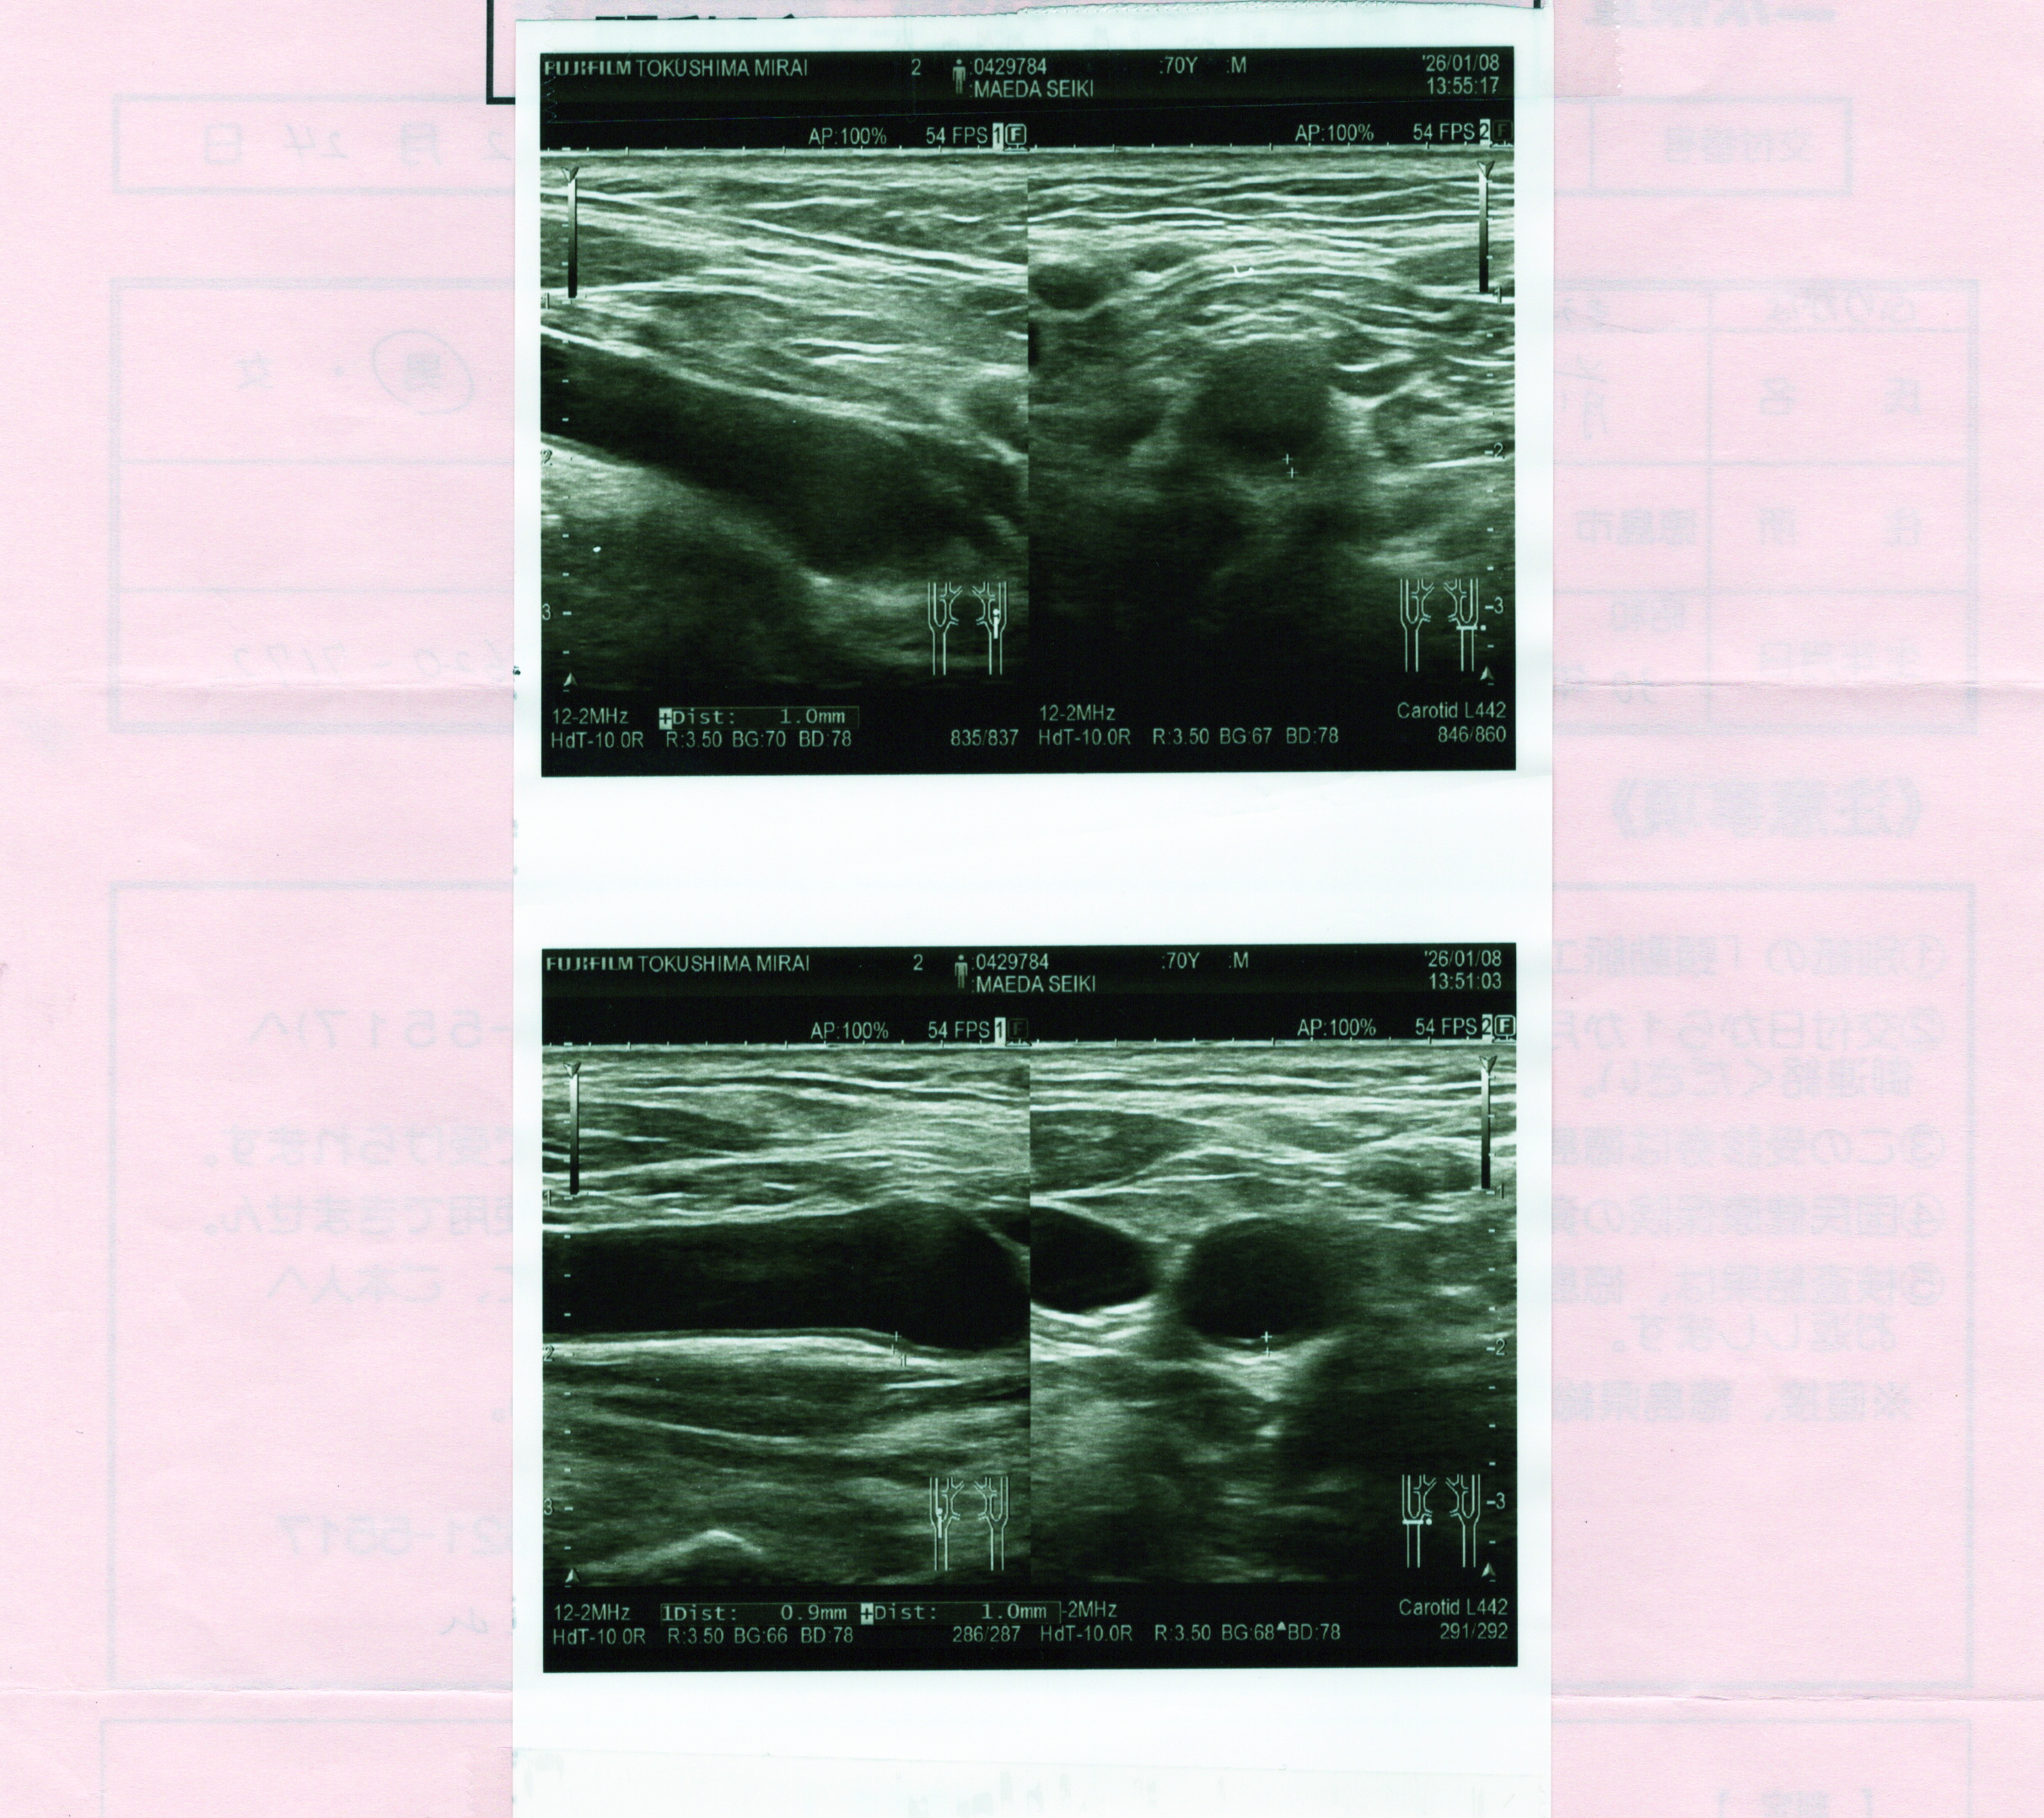

まずは頸動脈エコー検査の結果を見せていただきました。検査当日に担当医師から問題なしと聞いていたとおり、異常なしで特記すべき所見なしとの結果でした。

検査報告書の裏にはエコー検査の時に撮影した写真が添付されていました。これも当日の説明の時に見せていただいたものです。

左右の頸動脈の部分毎の血管の壁の厚みと血管の中にコレステロールが溜まっていないかどうか、そのために血管が狭くなっていないか(狭窄率)が判るようになっています。これを見ると血管の壁は0.4mmから1.0mmの間にあることが判ります。この数値に対する評価の説明資料もいただきました。

この説明によると私の場合、S1は0.4mm〜0.7mmで20代、S2は左右とも1.0mmで50代、S3は0.7mm〜0.8mmで30代、S4は0.5mm〜0.6mmで20代と年齢に比べると良好な状態にあることが判りました。血管にはプラークもなくて狭窄も起こっていないようです。